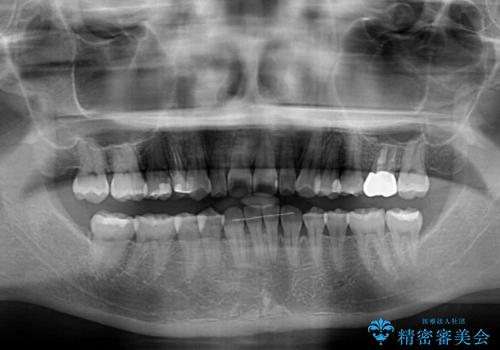

下顎前歯2本が先天欠損しており、上顎歯列に対して、下顎歯列がアンバランスに小さい状況でした。

左右上顎側切歯2本が矮小歯であるため、上顎の抜歯ではなく、IPR(歯と歯の間を削る)と歯列全体の後方移動によってバランスを整えることとしました。

歯列のバランスが悪く、インビザライン矯正特有の奥歯の噛みにくさがなかなか改善されず、治療期間が長期化してしまいました。